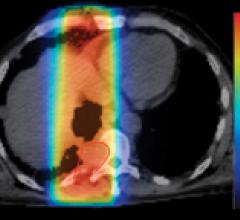

TomoTherapy Incorporated develops, markets and sells advanced radiation therapy solutions that can be used to treat a wide variety of cancers, from the most common to the most complex. The ring gantry-based TomoTherapy® platform combines integrated CT imaging with conformal radiation therapy to deliver sophisticated radiation treatments with speed and precision while reducing radiation exposure to surrounding healthy tissue. TomoTherapy’s suite of solutions include its flagship Hi·Art® treatment system, which has been used to deliver more than three million CT-guided, helical intensity-modulated radiation therapy (IMRT) treatment fractions; the TomoHD™ treatment system, designed to enable cancer centers to treat a broader patient population with a single device; and the TomoMobile™ relocatable radiation therapy solution, designed to improve access and availability of state-of-the-art cancer care.